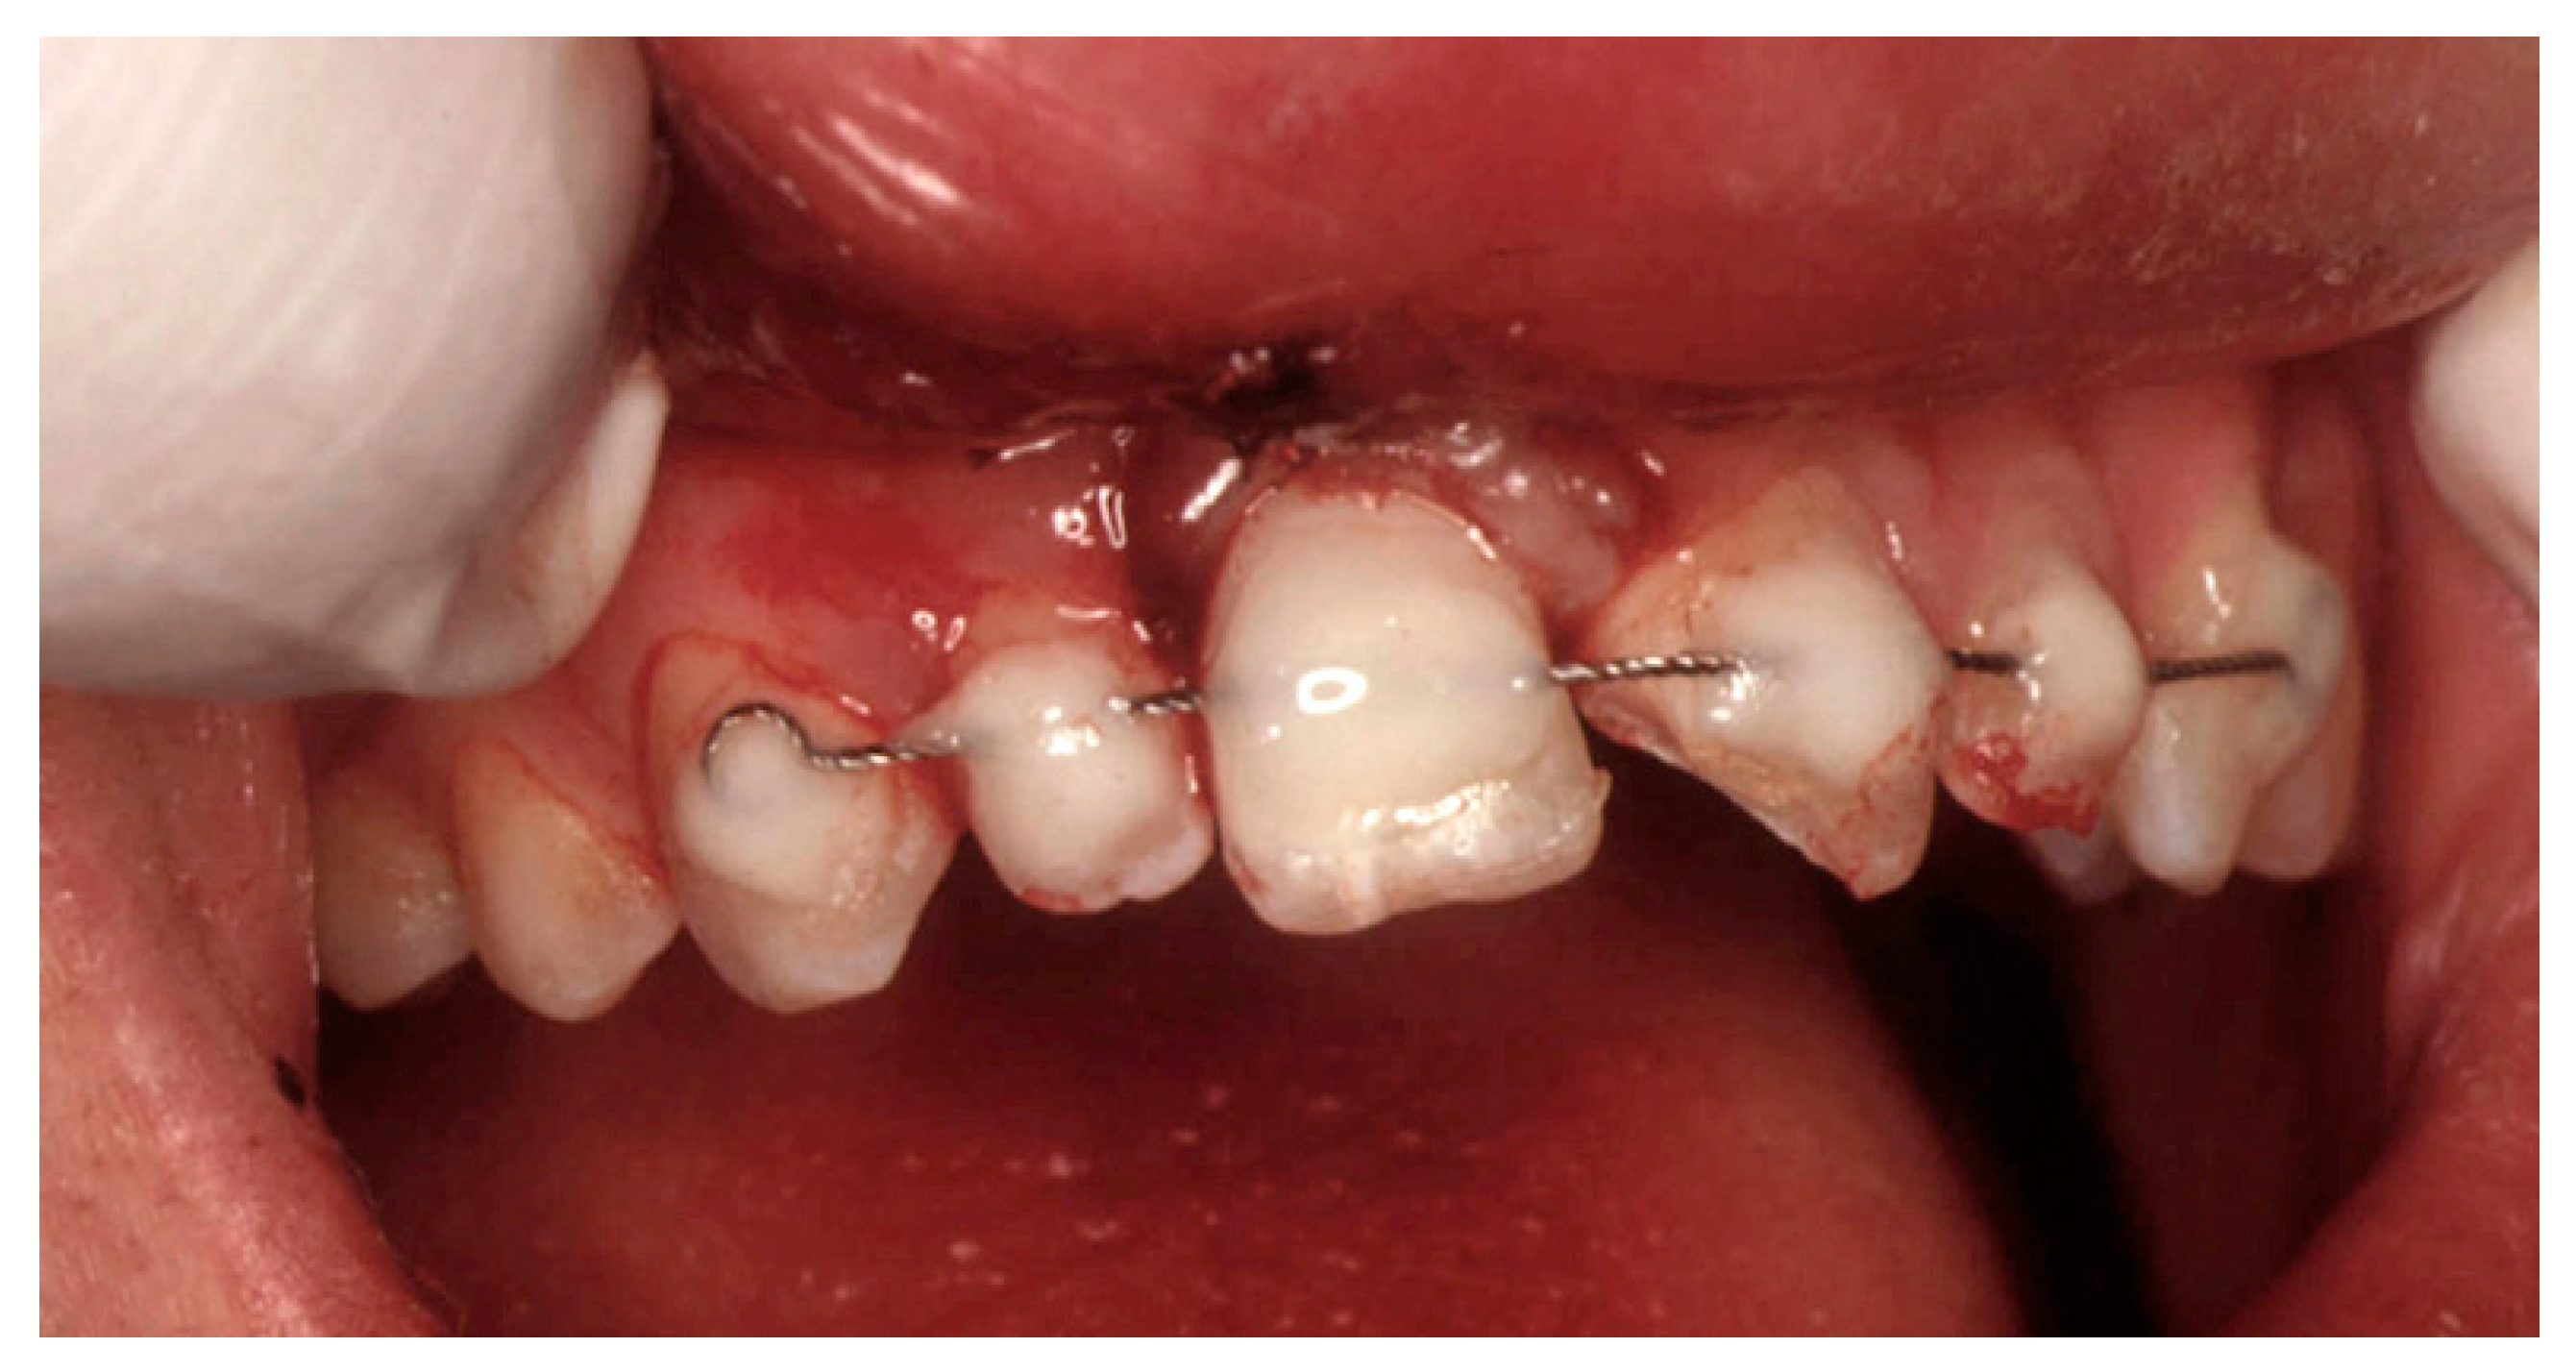

Survival of a Maxillary Incisor in an Adolescent Male 16 Years after Its Delayed Replantation

2. Case Presentation